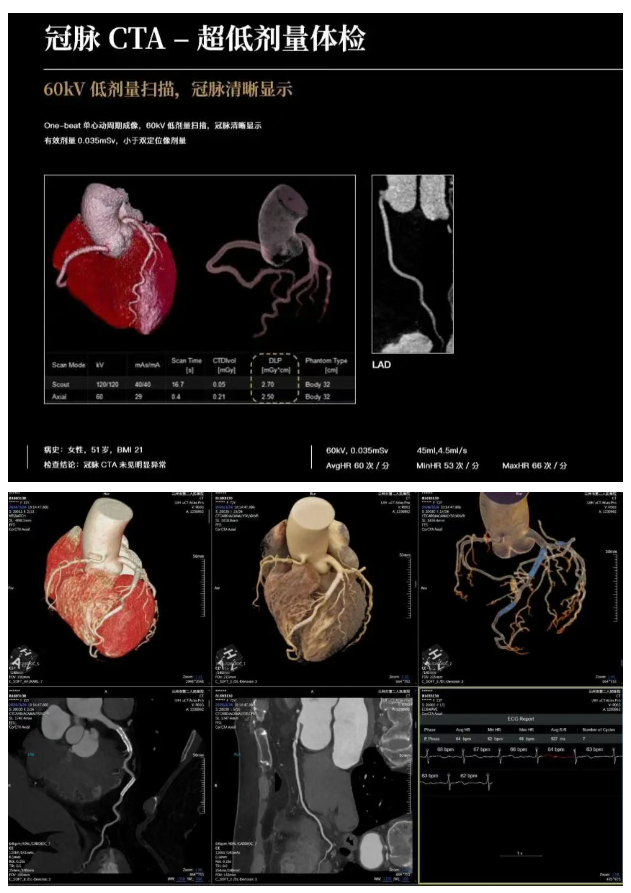

该设备业内领先的双精度图像感知平台,融合“AI深度学习”与“全模型迭代”双重技术优势,在降低辐射剂量的同时,还能显著提升图像质量。

对于肿瘤、心脑血管疾病等重大病症的早期微小病灶,能够实现精准捕捉与清晰显示,为疾病的早发现、早诊断、早治疗提供可靠的影像依据,既减少患者检查时的辐射暴露风险,也让临床诊疗更有科学支撑。